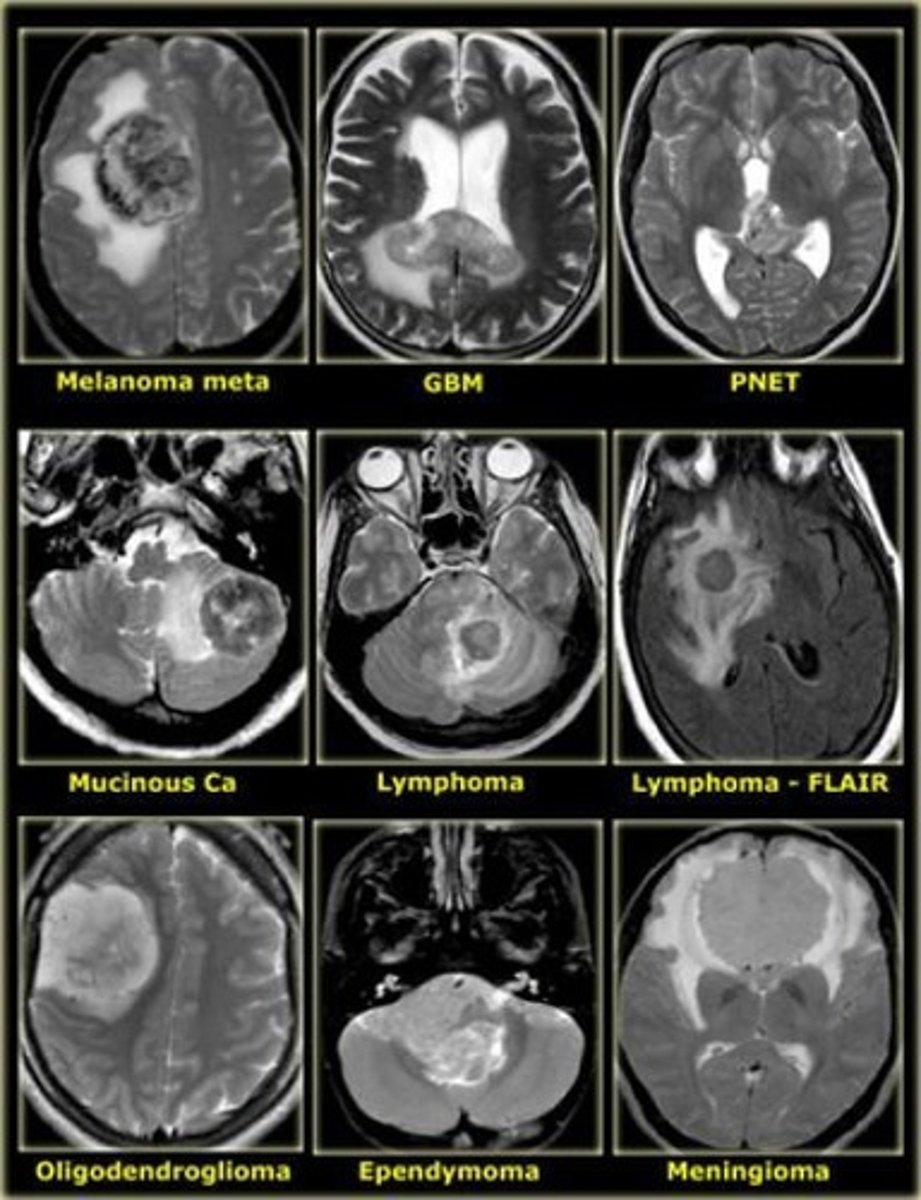

What is a glioma?

What is a meningioma?